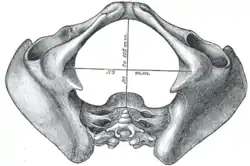

| Pelvic outlet | |

Diameters of inferior aperture of lesser pelvis (female) | |

The lower circumference of the lesser pelvis is very irregular; the space enclosed by it is named the inferior aperture or pelvic outlet. It is an important component of pelvimetry.

It has the following boundaries:

- anteriorly: the pubic arch

- laterally: the ischial tuberosities

- posterolaterally: the inferior margin of the sacrotuberous ligament

- posteriorly: the anterior border of the middle of the coccyx.[1]

When the ligaments are in situ, the inferior aperture of the pelvis is lozenge-shaped, bounded as follows:

- in front, by the pubic arcuate ligament and the inferior rami of the pubes and ischia

- laterally, by the ischial tuberosities

- behind, by the sacrotuberous ligaments and the tip of the coccyx.